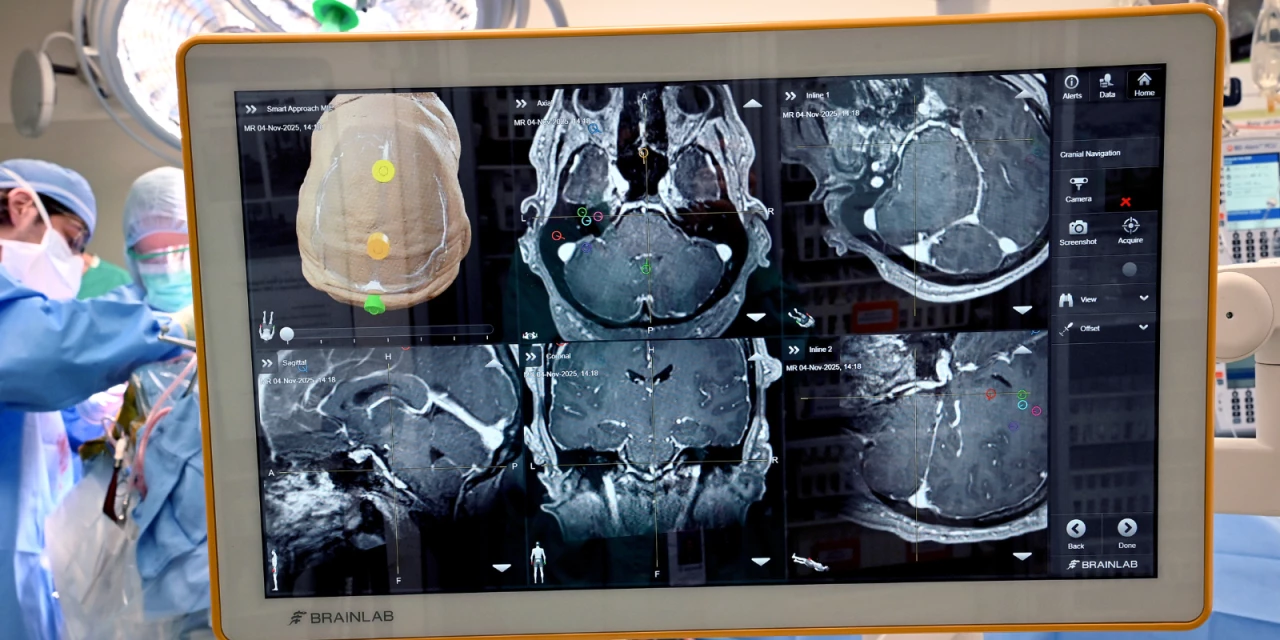

Neurosurgeons at UCHealth University of Colorado Hospital and the CU Anschutz School of Medicine performed Colorado’s first implanted brain–computer interface (BCI) surgery, placing an implant that will record and stimulate the patient’s brain to restore motor and sensory function.

Physicians said the implant site is notable. “While most BCI procedures focus only on purely motor regions, implanting this device in higher‑level brain areas will offer new insights into how the human brain works during everyday thinking and movement,” said Daniel Kramer, MD, assistant professor of neuroscience and a neurosurgeon at UCHealth.